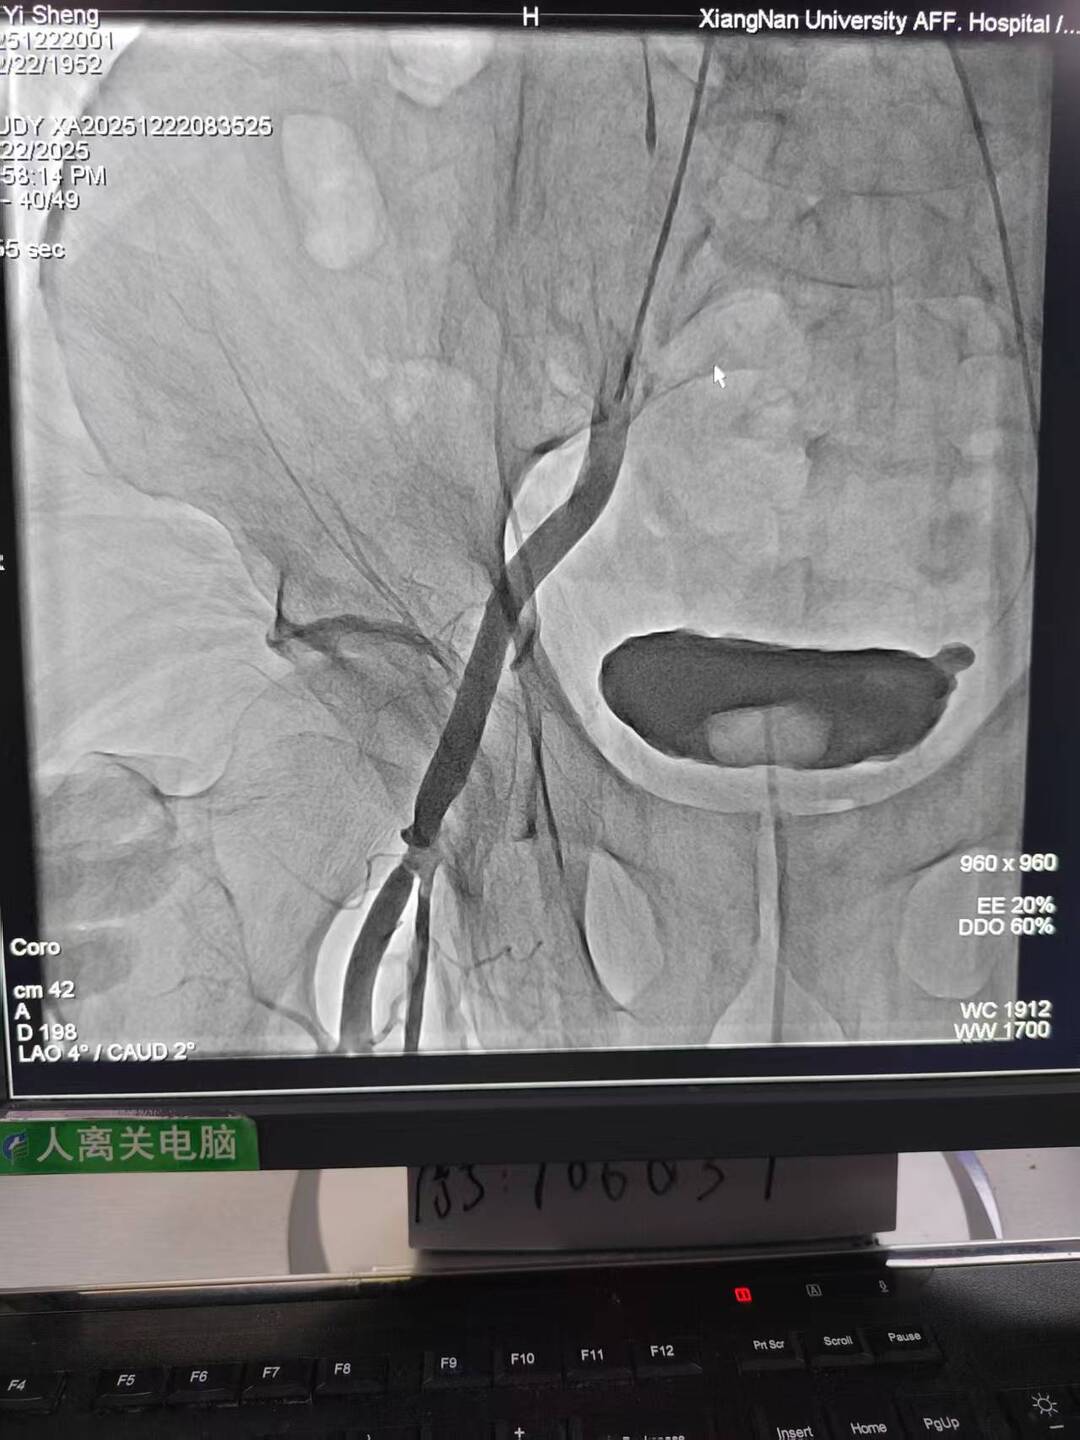

手术过程犹如在心脏内进行的“微雕”和“换门”工程,步骤环环相扣,每一步都考验着术者的技术功底与团队协作默契。术中,团队首先利用先进的可扩张血管鞘,在严重钙化狭窄的右侧股动脉腔内成功建立安全的手术通路;随后经该微创入路,先通过球囊扩张术为冠状动脉植入支架,快速恢复心肌血供;紧接着,在同一手术台、同一入路下,精准将人工主动脉瓣输送至病变位置并成功释放,顺利替换失灵的原生瓣膜。整个过程中,团队成功克服了外周血管入路困难的核心挑战,确保手术各环节无缝衔接、精准落地。

术后,患者主动脉瓣功能即刻恢复正常,冠状动脉血流重回通畅,胸闷、气促等不适症状显著缓解。经过后续康复护理,患者已顺利出院,重获正常生活能力。